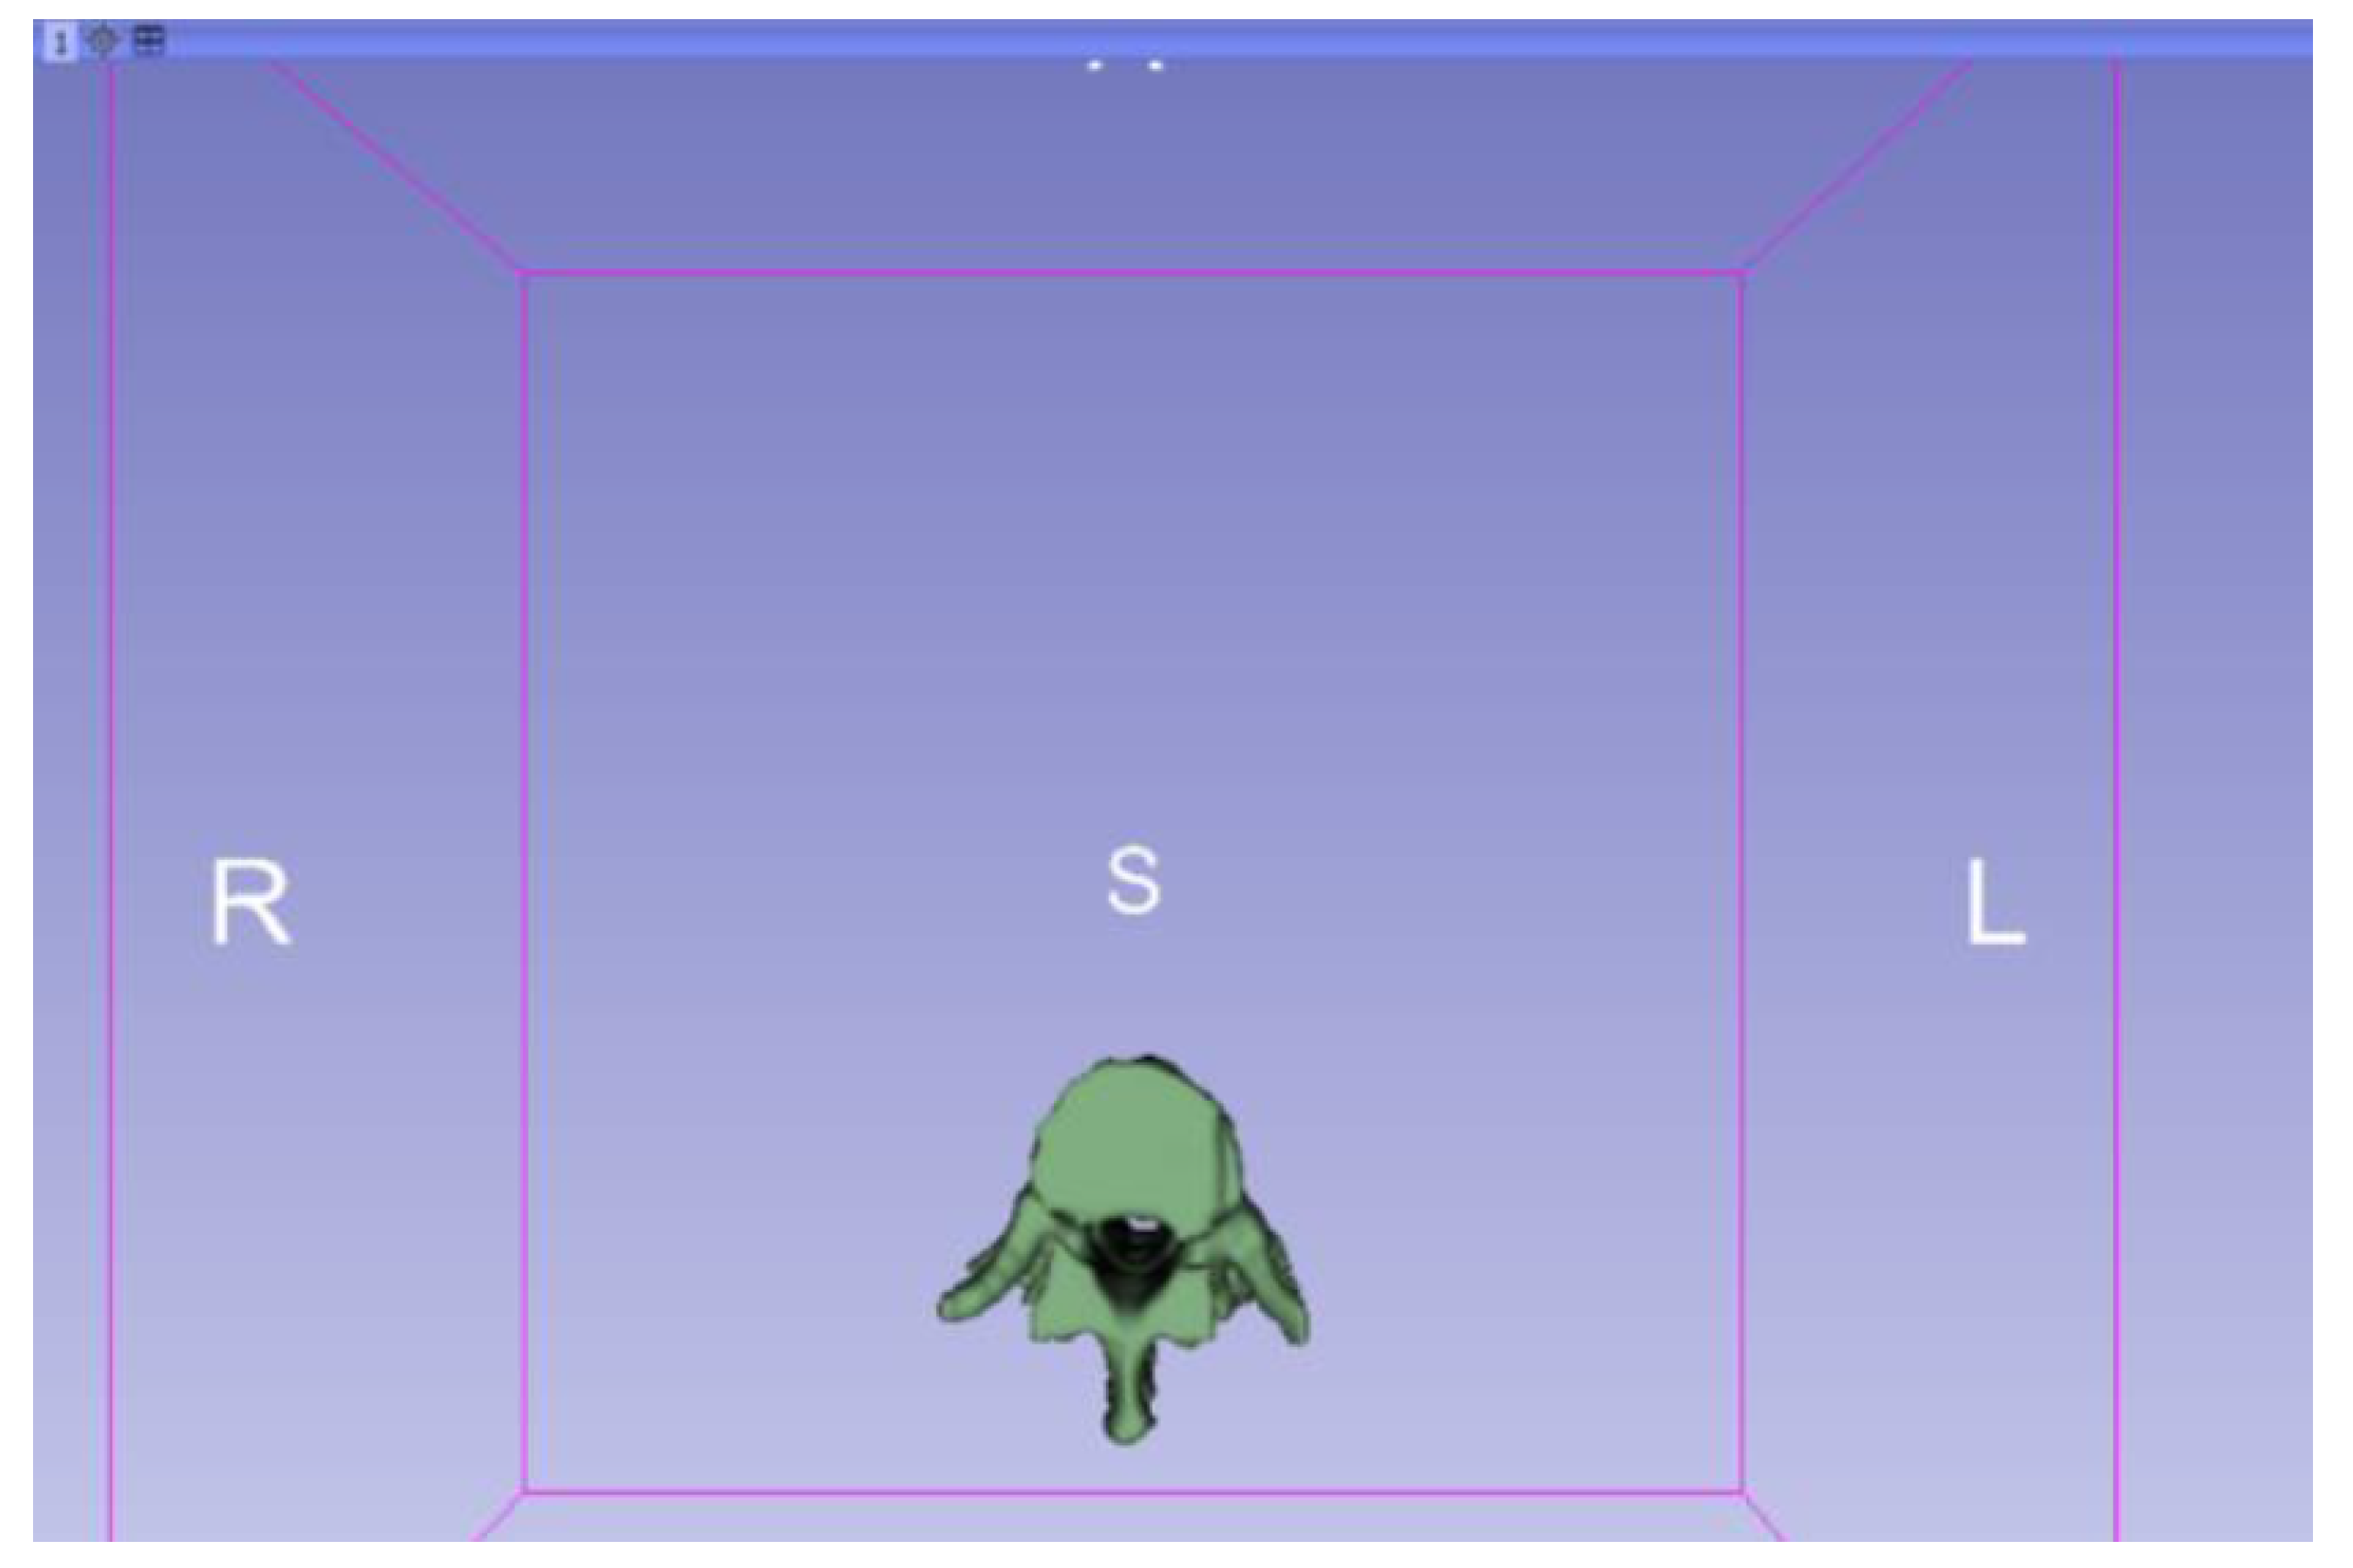

3.1.1. DICOM-to-STL File

| Vertebrae | [150, 300] | Median | 0.8 | 0.18 | 25 |